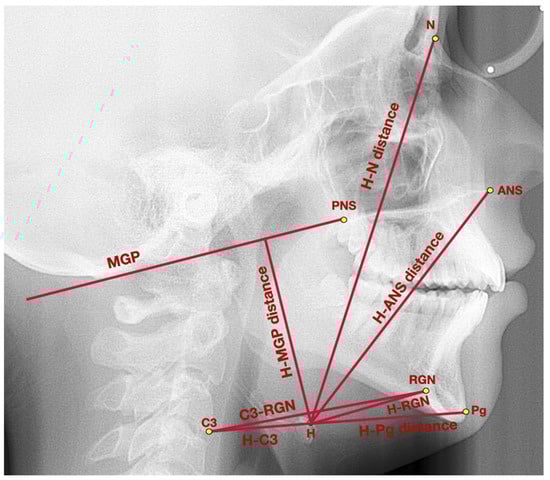

| General points and lines | Point ANS | Anterior nasal spine–the most prominent point of the anterior nasal spine |

| Point PNS | Posterior nasal spine–the most posterior point of hard palate, crossed by the pterygopalatine fossa | |

| Point Pg | Pogonion–the most prominent point localized in the mental tuberosity | |

| Point N | Nasion–the most anterior point localized in the frontonasal suture | |

| Point H | Hyoidale–the most superior anterior point of the body of the hyoid bone | |

| Point C3 | The most inferior anterior angle of the body of the third cervical vertebra | |

| RGN | Retrognathion–the most posterior inferior aspect of the mandibular symphysis | |

| MGP | McGregor’s Plane–line which links posterior nasal spine with the basiocciput | |

| Hyoid triangle | H-C3 distance | The distance between the points: H and C3 |

| H-RGN distance | The distance between the points: H and RGN | |

| C3-RGN distance | The distance between the points: C3 and RGN | |

| H-H’ distance | The height of the hyoid triangle, measured as a distance between point H and the perpendicular projection of point H onto C3-RGN line | |

| Hyoid bone topography | H-MGP distance | The distance measured between point H and the perpendicular projection of point H onto MGP |

| H-N distance | The distance between the points: hyoidale and nasion | |

| H-ANS distance | The distance between the points: hyoidale and anterior nasal spine | |

| H-Pg distance | The distance between the points: hyoidale and pogonion | |